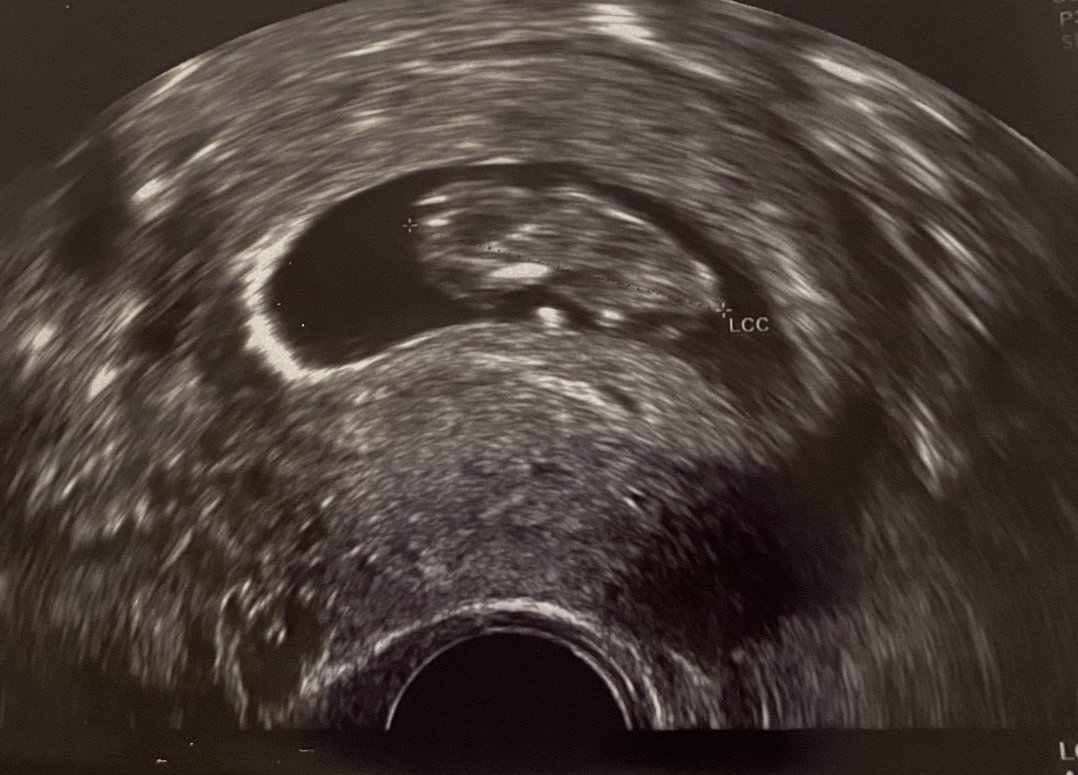

Знае ли се пола или е рано още?